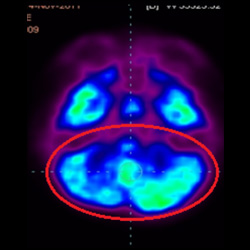

細胞治療前PET CT掃描顯示神經(jīng)組織中的藍/黑色區(qū)域,表明腦癱引起的大腦損傷。

腦癱細胞療法, 腦癱治療

細胞治療后,藍色和黑色區(qū)域減少,并且看到更活躍的區(qū)域。這表明損傷減少并改善了大腦功能。